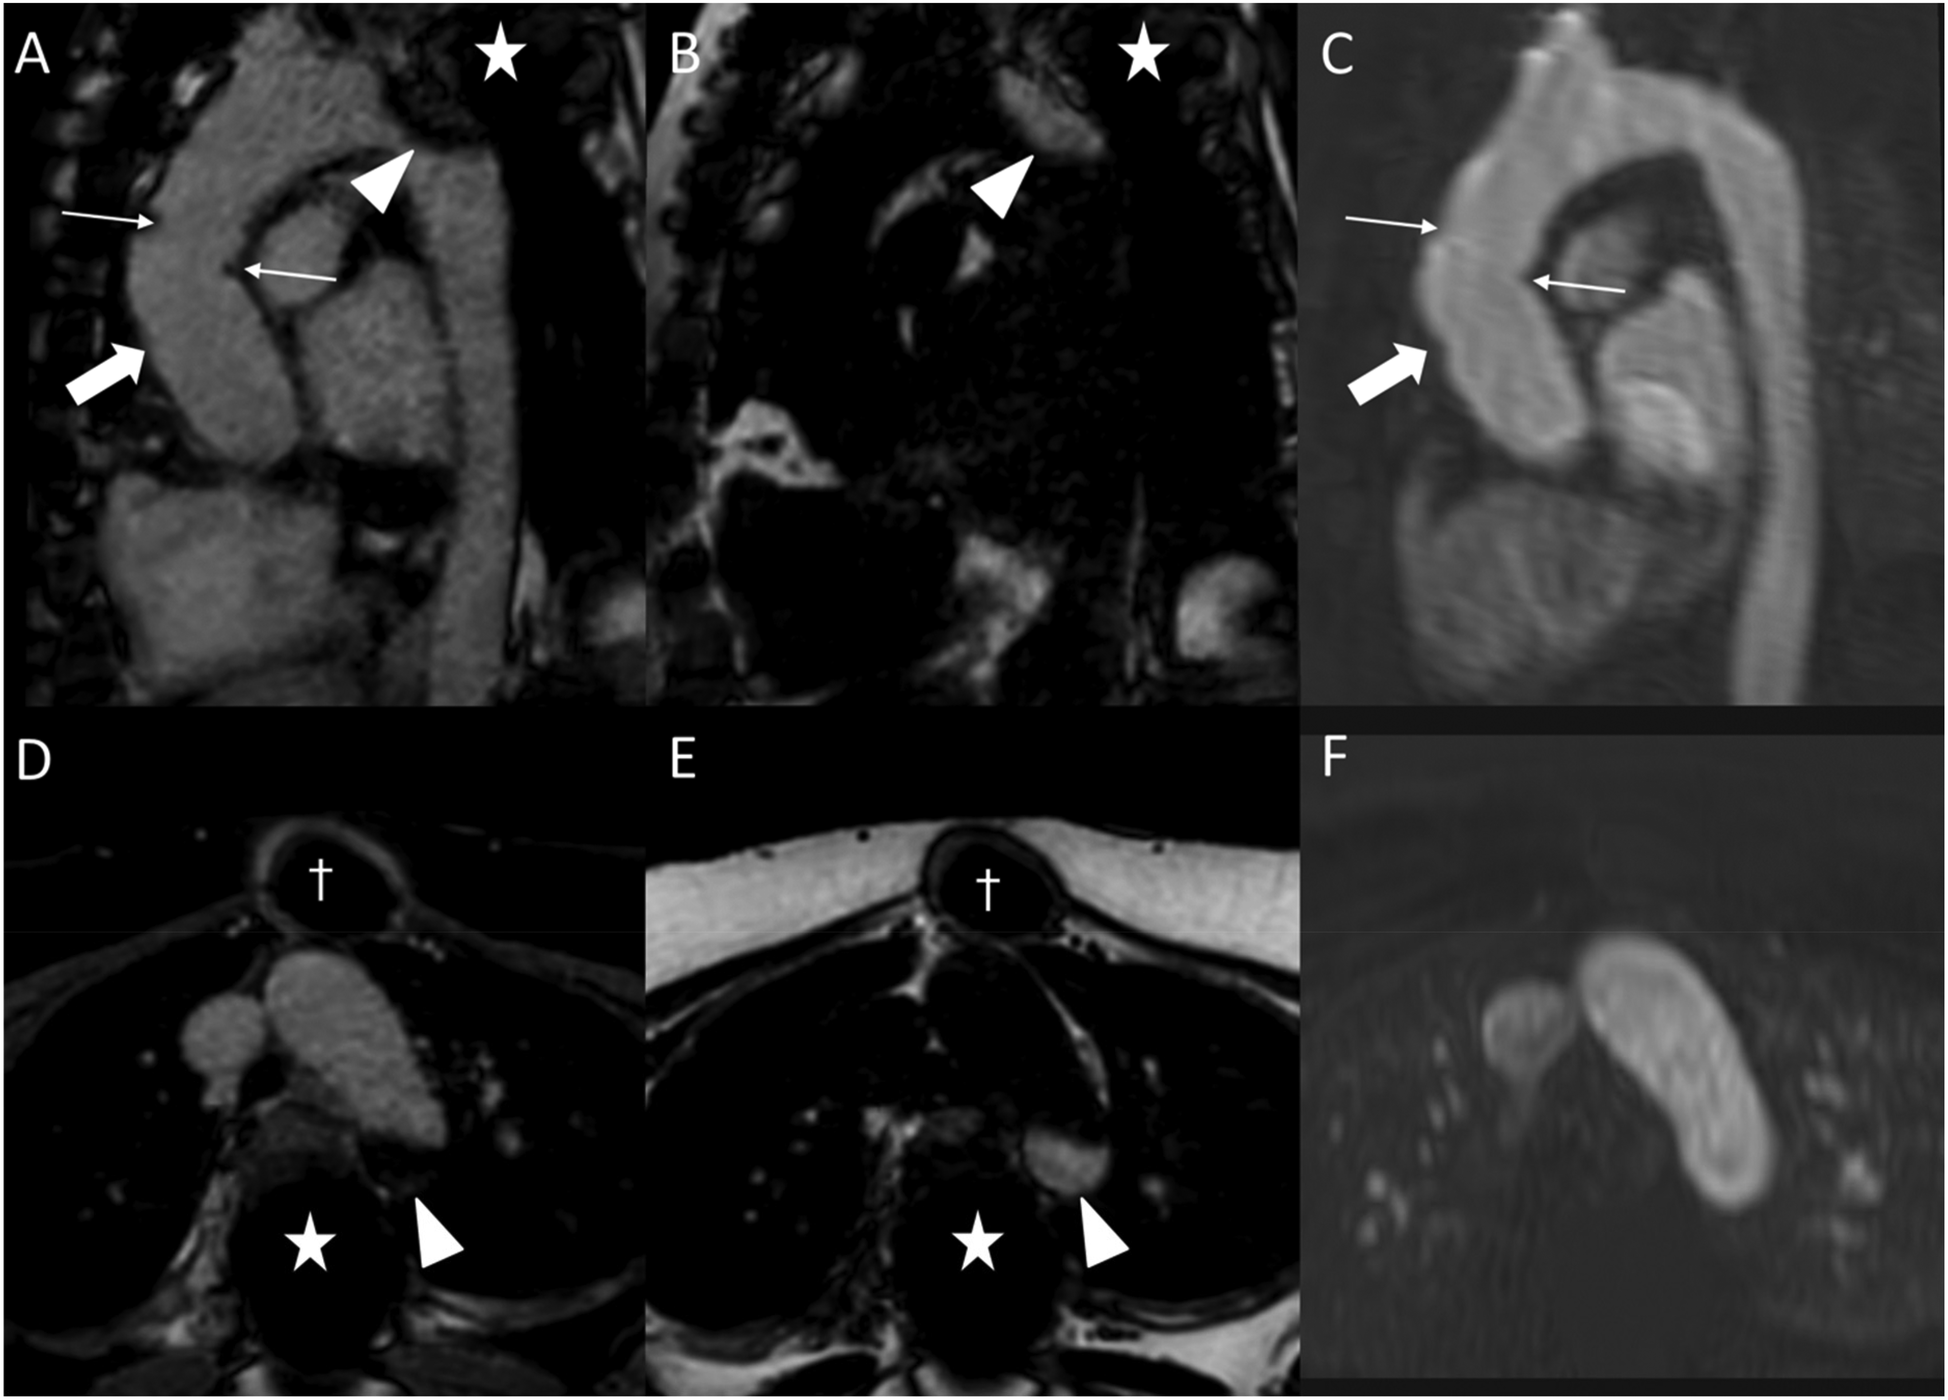

Figure 7

Fat-water separation artifact in REACT as shown in parasagittal reformations (A–C) and axial source images (D–F) in a 41-year-old female with Marfan syndrome after bentall procedure due to Stanford type A aortic dissection. While the REACT sequence [(A) and (D), water-only images; (B,E) fat-only images] enables a superior delineation of the distal anastomosis (wide arrow: mid graft, thin arrows: distal anastomosis) compared to CE-MRA (C,F), the aortic graft is apparent in both sequences. Furthermore, there is a signal loss at the aortic arch in the water-only images of REACT (arrowheads) due to spinal fusion (asterisk) with corresponding fat-only images showing a hyperintense signal, clarifying the drop-out as an artifact. Note that the susceptibility artifacts from sternal wires (daggers) do not hamper the image quality of REACT. CE-MRA, contrast-enhanced magnetic resonance angiography; REACT, relaxation-enhanced angiography without contrast and triggering.